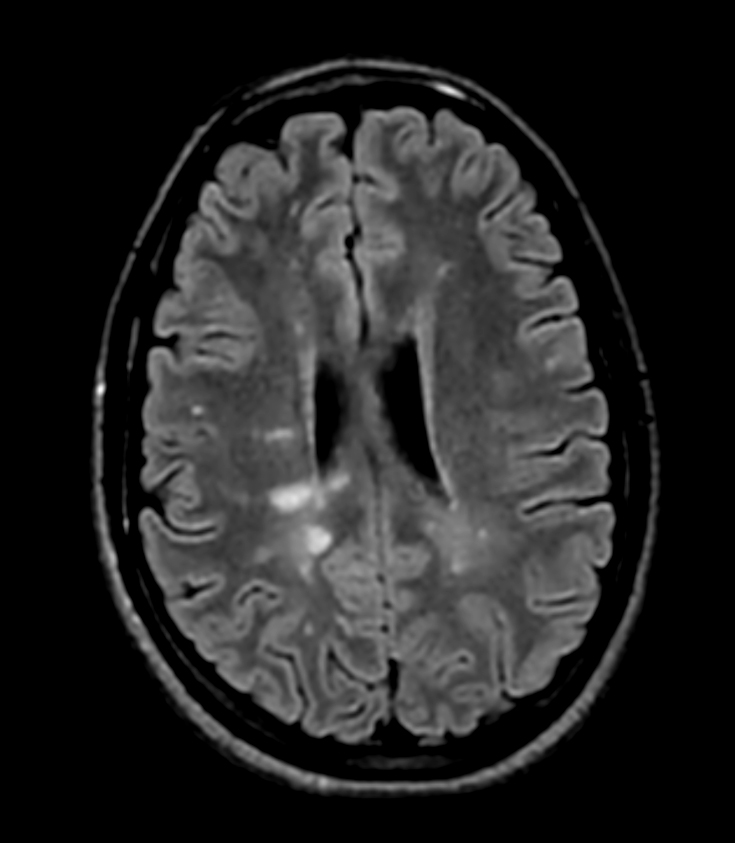

Patient with multiple brain lesions. ExamCard includes Compressed SENSE to shorten the exam time, 3D scans to acquire high resolution data in multiple directions in only one single scan and 4D-TRAK for dynamic contrast-enhanced MR Angiography enabling high spatial and temporal resolution simultaneously.

DWI (ADC)